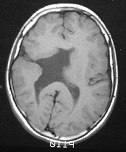

Mapeamento cerebral com EEG para estudo do aprendizado da leitura

Diagnóstico